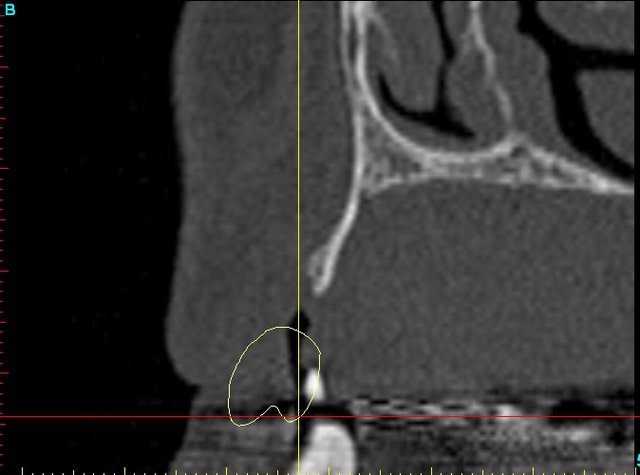

Dar12 dmdcf3 - Eugenol

Dar13 snfr77 - Eugenol

12dar ujxzdu - Eugenol

13dar zaa5vz - Eugenol

22dar mrs1pw - Eugenol

Darcl12.12 - Eugenol